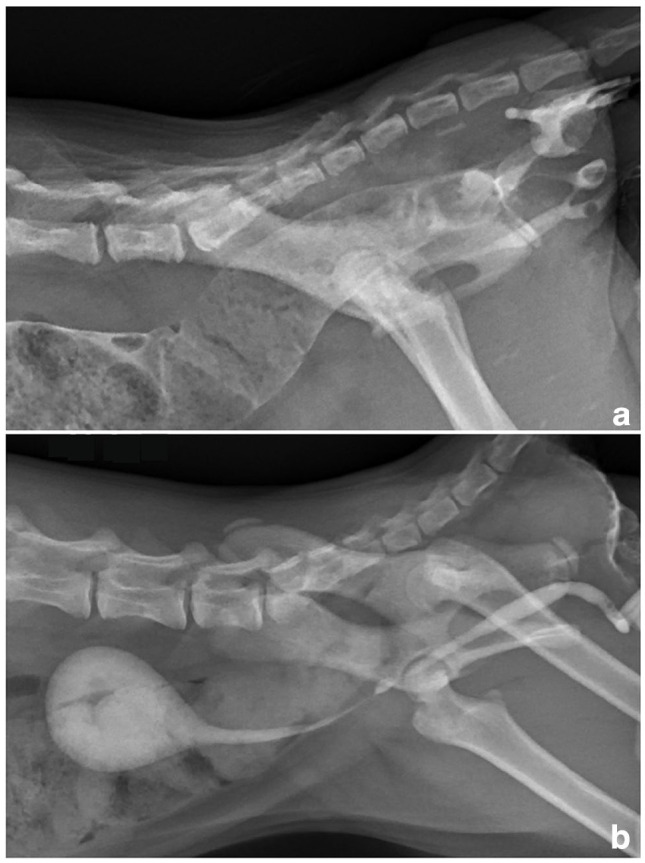

病例总结:一只2个月大的雄性英国短毛猫被怀疑患有肛门闭锁。体格检查发现肛门不穿孔,并有少量粪便通过阴茎排出。x线表现,连同逆行尿道造影,证实诊断为II型闭锁伴尿道直肠瘘。手术后患者恢复良好。8个月大时,先天性尿道直肠瘘经会阴单路手术治疗,包括经同一切口行瘘管切除术和去势。术后短期预后良好,排便和排尿正常。相关性和新信息:闭锁是一种罕见的先天性异常,特别是在公猫。尽管手术技术取得了进步,但该病例是首例成功分阶段手术治疗雄性小猫II型闭锁尿道直肠瘘的病例,可能影响未来类似先天性异常的手术入路。

Case summary: A 2-month-old male British Shorthair cat was referred with suspected atresia ani. Physical examination revealed an imperforate anus and dribbling of faecal discharge through the penis. Radiographic findings, along with a retrograde urethrogram, confirmed the diagnosis of type II atresia ani with a urethrorectal fistula. Surgical anoplasty was performed and the patient recovered well. At 8 months of age, surgical treatment for the congenital urethrorectal fistula was carried out via a single perineal approach, including fistulectomy and castration through the same incision. Postoperative short-term outcomes were excellent, with normal defecation and urination.